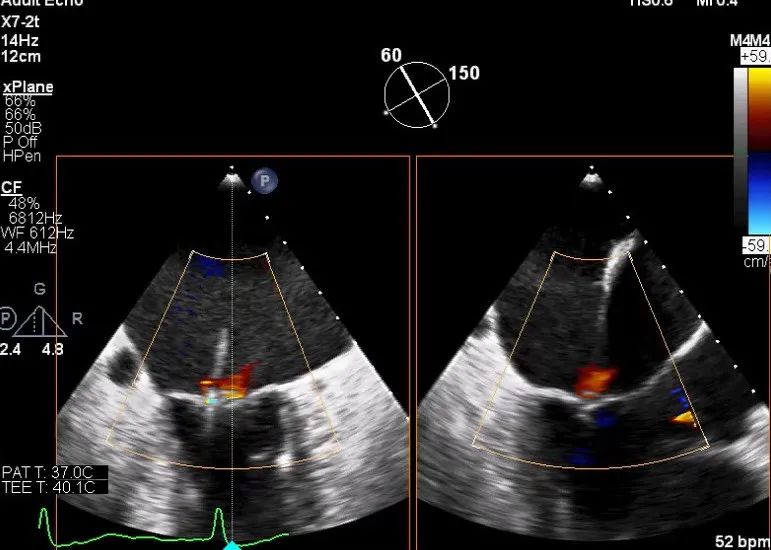

TEE LVOT切面返流量评估

TEE 4-Ch view返流量评估

X-plane:下第夹子尝试捕获2区

X-plane:测量前叶长25mm,后叶长14.2mm

X-plane:计算前叶捕获长度8mm,后叶捕获长度7mm

3D视图下观察二尖瓣双孔形态

3D-color:残余少量返流